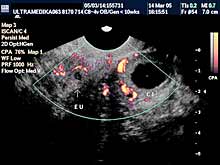

A) I trimestar do 14

nedelje gestacije

(3 meseca + 2 nedelje)

Indikacije za ultrazvučni pregled:

- Izostanak menstruacije, procena vitalnosti rane trudnoće,

procena materične i/ili postojanje vanmaterične trudnoće.

(Od 4-7 nedelje gestacije, ili prva 2 meseca od prvog dana zadnje

menstruacije).

- Prva procena posteljične cirkuacije Broandband - CD

Način pregleda:

- transabdominalno i/ili endovaginalno

(bez prethodnog punjenja

mokraćne bešike).

Primenjena tehnika:

- Broadband 2D,

- harmonik mod,

- Sono CT,

- XRes,

- 3D Sono CT,

- CPA.